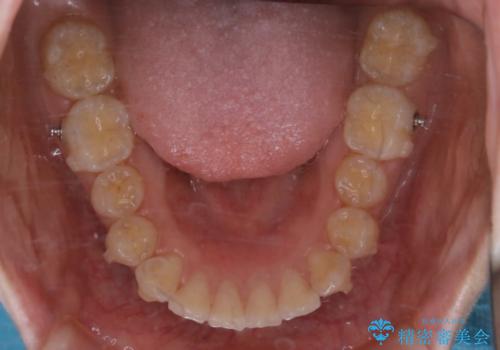

- 前歯の重なりが気になるとご相談にいらした方です。前歯のがたつきは奥歯の噛み合わせのズレが原因となっていたため、インビザラインFULLにて奥歯からしっかり治療していきました。

前歯のがたつきだけを治そうとした場合、噛み合わせは二の次なってしまう事が多く、せっかく綺麗になった歯並びも後戻りしやすくなります。

見た目だけでなく奥歯を移動させて噛み合わせの改善までが行えるのはインビザラインであるからこそです。奥歯の噛み合わせからしっかり機能させることで、長期間にわたって綺麗な歯並びを保ちやすくなります。